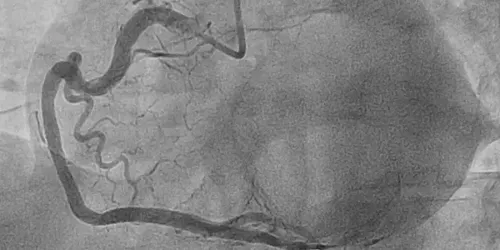

The performance of catheterizations, in most patients by radial access (through an artery in the wrist), makes it possible to identify whether there are significant obstructions in the coronary arteries. If this is the case, we have the latest techniques to assess the need for implantation of pharmacoactive stents to solve the problem.

Percutaneous intervention of coronary artery lesions is today the mainstay of treatment of coronary disease.

The procedure consists of accessing with a catheter (very thin flexible tube), through a puncture in the radial or femoral artery, until reaching the origin of the coronary arteries in the aorta, next to the heart. Afterwards, the narrowed or obstructed areas are usually dilated with a small balloon, and then one or more stents are implanted to achieve an optimal result. The stent allows the obstruction to be prevented from reappearing in a percentage of more than 95% of injuries.